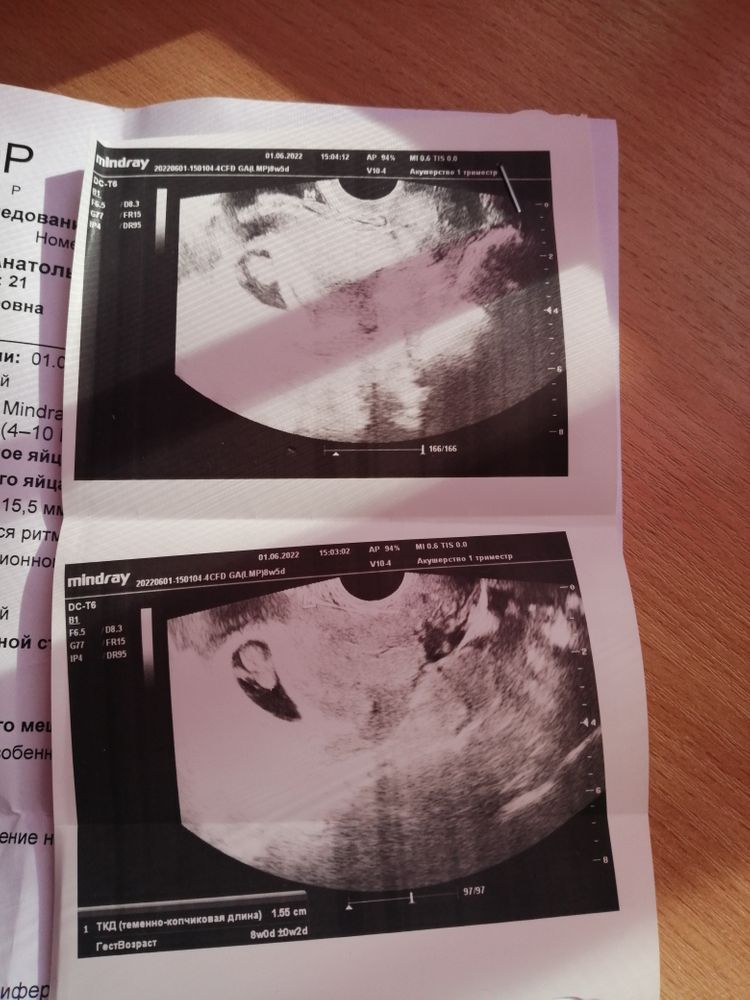

Была сегодня на узи, срок по м 8н5д, так же была неделю назад у этого же врача, ктр был 6.3, свд 3.1. Врач сказала беременность развивается хорошо, все нормально, без патологий, ни о чем можно не переживать, дала послушать сердечко. И тут как гром среди ясного неба говорит, вижу небольшой тонус по передней стенке 😑, на 2х предыдущих ничего такого не было. В целом меня ничего не беспокоит, живот не каменеет, не тянет, не болит, выделений подозрительных нет. Не понимаю откуда он взялся и насколько это опасно. Теперь сижу и переживаю, поставила в заключении угрозу прерывания🥺. Она как то легко об этом сказала, особо не заостряла внимания, а я теперь на нервах. Говорит если вы так сильно переживаете, давайте я в заключении напишу угроза🤷🏼

Очень похожи фото узи на мои на таком же сроке. И тоже сказали «тонус по передней стенке», пытались даже на таких фото показать мне, где там тонус- я не поняла) но не пугали. Я накануне, извините, вся ублевалась из-за токсикоза, гиня сразу сказала, что тонус из-за рвоты. Я тоже не ощущала ничего неприятного в животе. Для информации, что мне прописали: 5 дней пить но-шпу 3 табл в день + на ночь папаверин. Ну я дня три следовала указаниям галочки ради, а потом перестала. Лежала по возможности. Все хорошо, и у Вас всё хорошо 💗 здоровья!